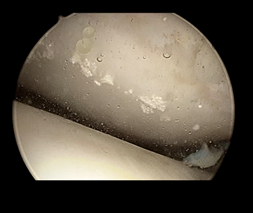

病例一:患者中年男性,左膝关节疼痛不适2年余。术前查血尿酸620umol/L,术前MRI和CT检查均未见明显异常。在行关节镜手术中,见大量痛风结晶沉积在软骨、韧带、半月板、滑膜表面!

使用刮匙清理关节痛风结晶: